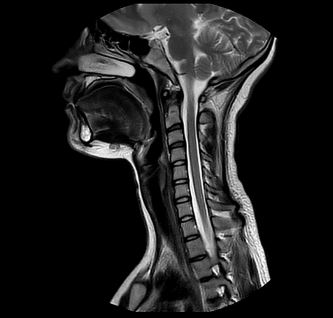

Beispiele von MRT-Hals Aufnahmen

Bei einer MRT des Halses können nahezu alle anatomischen Strukturen zwischen Kiefer und Schlüsselbein dargestellt werden. Die exakte Abbildung dieser Strukturen erlaubt es, Veränderungen frühzeitig zu erkennen und gezielt zu behandeln.